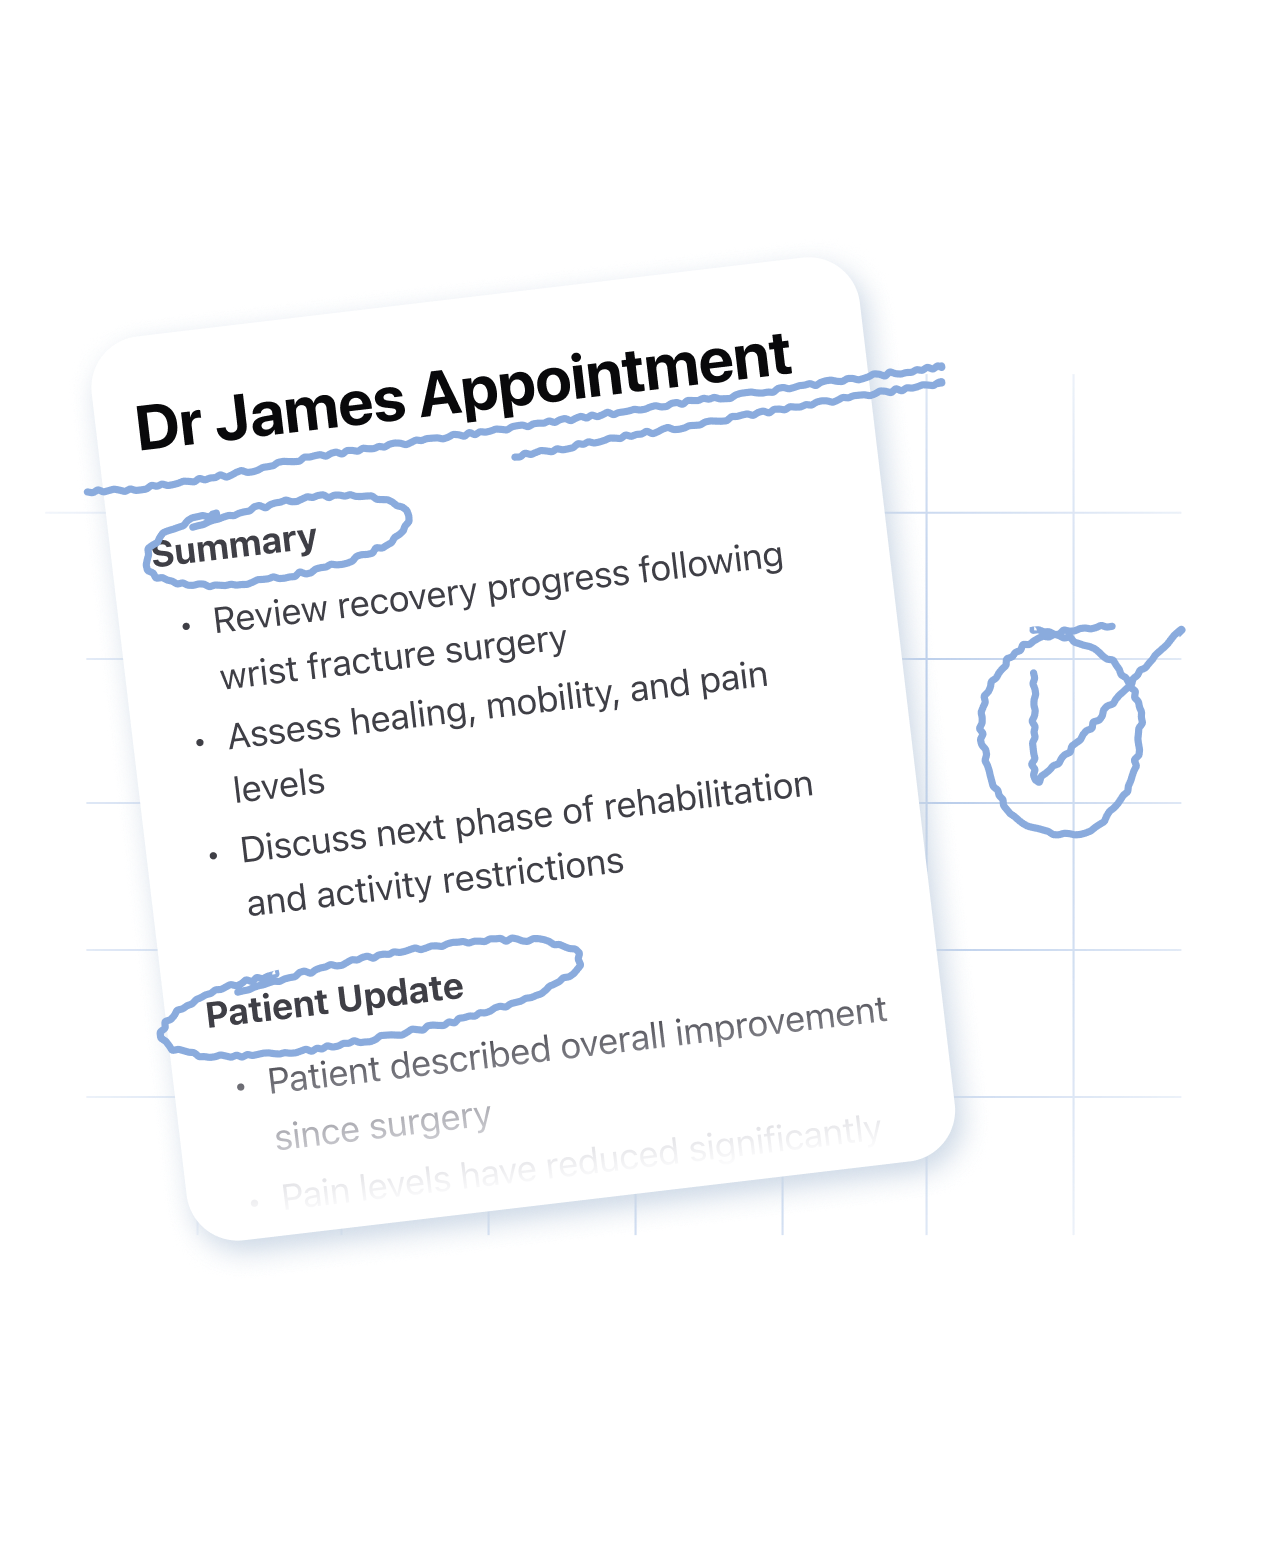

Doctor Appointments

Cue capture every detail, recommendations in your next doctor appointment